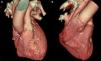

A 74-year-old man, with a history of heavy smoking, presented with unstable angina (Figure 1). Dobutamine stress echocardiography showed ischemia in the right coronary artery territory. Coronary angiography revealed no obstructive epicardial disease in the left dominant circulation (Figure 2A); the right coronary artery (RCA) was a small caliber and tortuous vessel, with only minor atheroma. However, an abnormal vessel arising from the proximal RCA was noted (Figure 2B and C), confirmed as a fistulous connection to the left atrium by multislice computed tomography, which also excluded other vascular anomalies (Figure 3). This was deemed to be causing a coronary steal phenomenon. Exercise myocardial perfusion imaging under anti-ischemic therapy excluded residual ischemia and the patient was successfully conservatively managed (Figure 4).